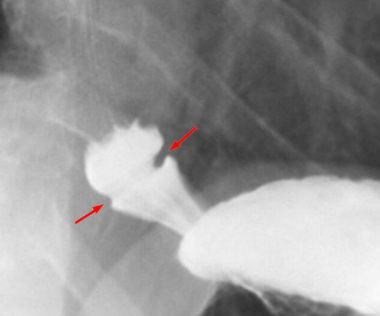

_____ diverticulum is an outpouching of pharyngeal mucosa through an acquired defect in the muscular wall (false diverticulum) caused by cricopharyngeal motor dysfunction